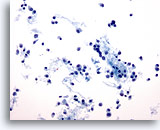

Figure 65

Breast FNA, Lymphoma.

This field shows scattered cells with very little cytoplasm. No clusters are present. The cells have round nuclei with a margin of cytoplasm at one side. The features appear lymphoid rather than epithelial. 40x

Figure 65

Breast FNA, Lymphoma.

This field shows scattered cells with very little cytoplasm. No clusters are present. The cells have round nuclei with a margin of cytoplasm at one side. The features appear lymphoid rather than epithelial.

40x